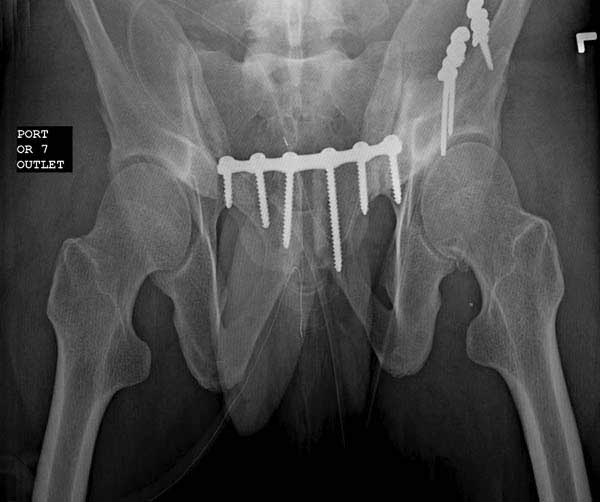

Здесь представлен случай 38 летнего больного (падение с высоты 9 метров) с нарушением тазового кольца. При поступлении для стабилизации передне-нижний аппарат наружной фиксации и на 6й день, вчера, операция из двух доступов.

Представлены снимки техники проведения стержней. Через место прикрепления прямой мышцы в Inferior Iliac Spine в направления вырезки создается жесткость. Weber clamp изнутри таза для репозиции, и фиксация после репозиции перелома крыла подвздошной кости. Наружный аппарат удален, нагрузка предполагается через два месяца.